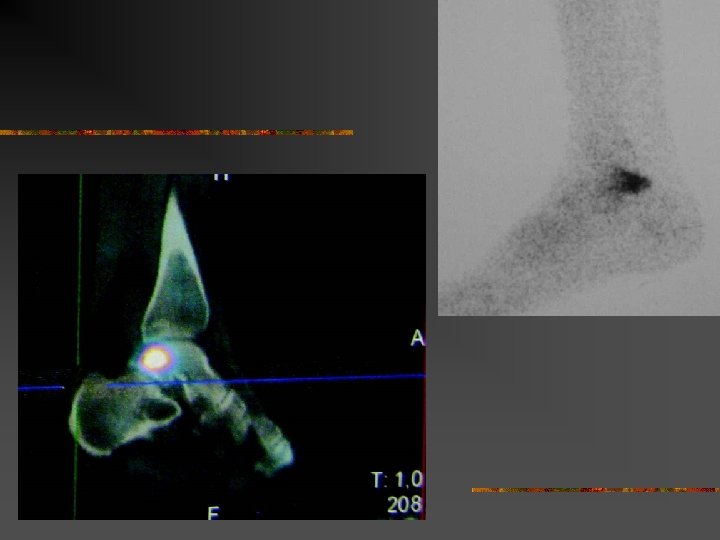

Le SCP traumatique : Mécanismes Trauma en flexion plantaire forcée n Très fréquent… n Origine : Shoot contré, tacles, irrégularité du sol, … Lésions : - contusion « postérieure » chondrales, caps. -ligamentaire - # processus post. lat. du talus (# de SHEPHERD) - # malléole tibiale postérieure - # os trigone ou de la synchondrose n Difficultés : - DD # ou os trigone… - Arguments : - # : trait net et non corticalisé - scintigraphie n

Fracture du processus postéro-latéral